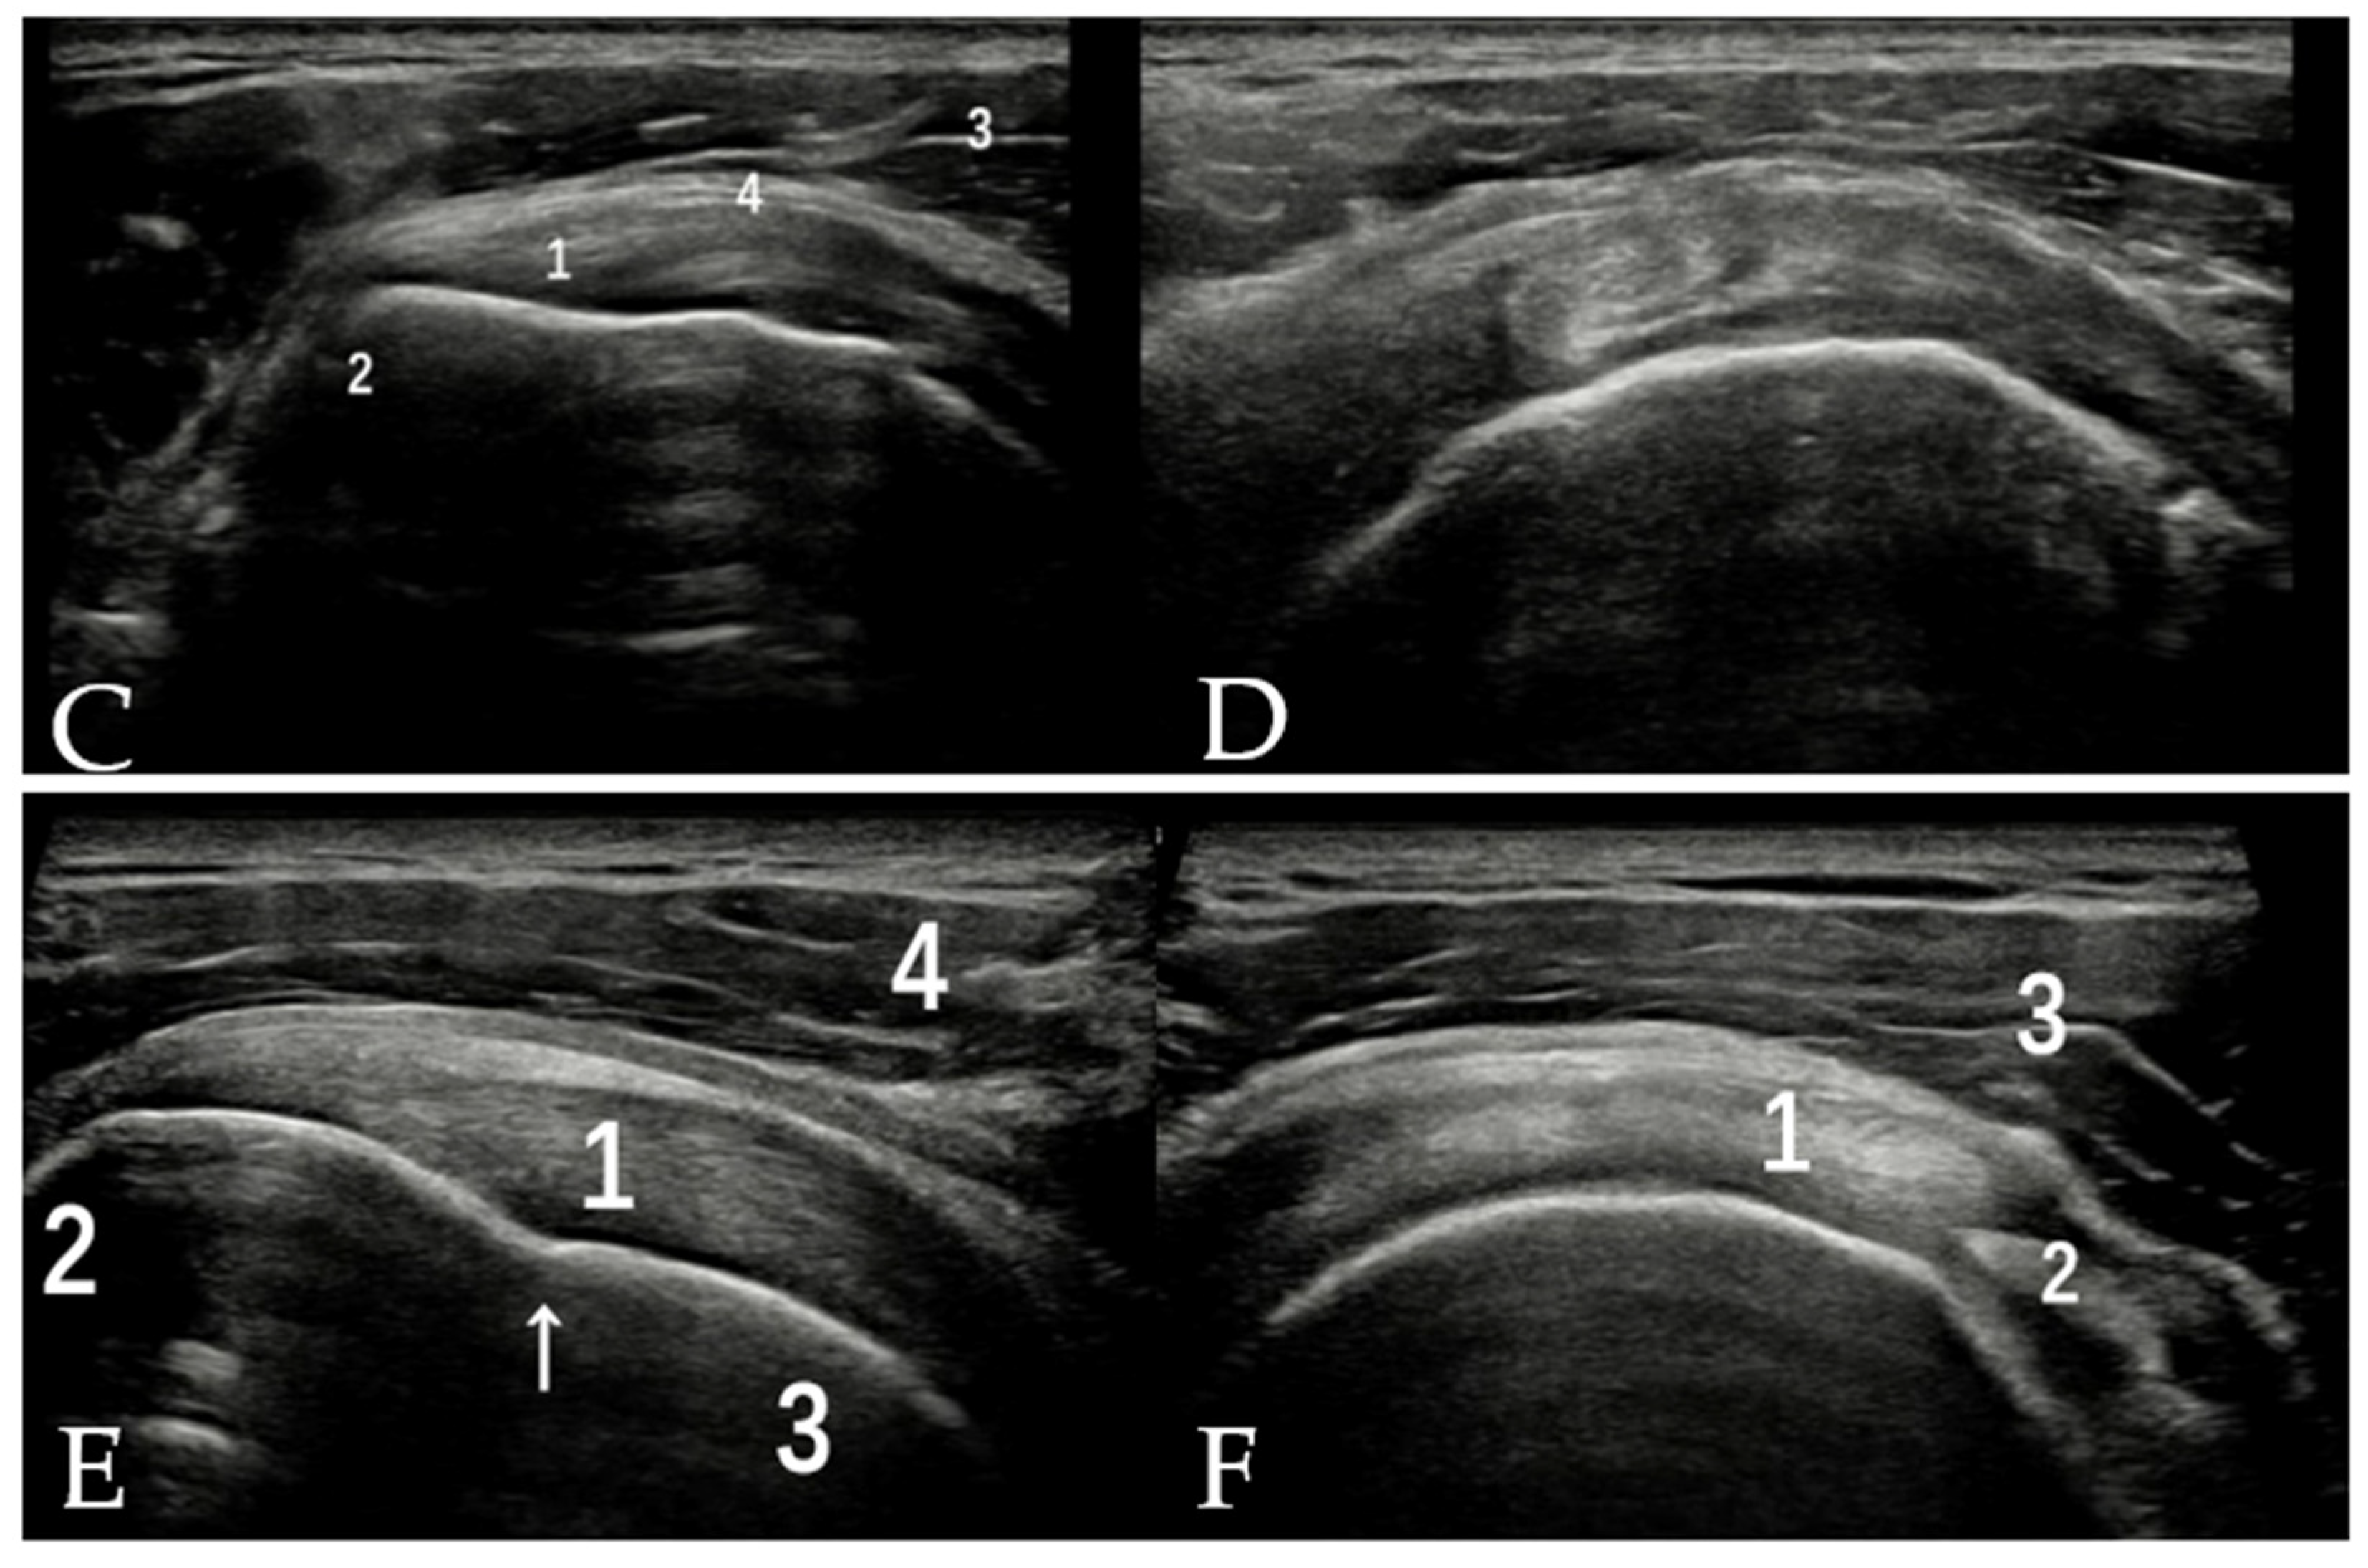

3.3. SSC and SSP Tendons

3.4. Tendon of PM

3.5. Tendons of LD and TM

4. Pathologic Conditions

4.1. Biceps Pulley Lesions